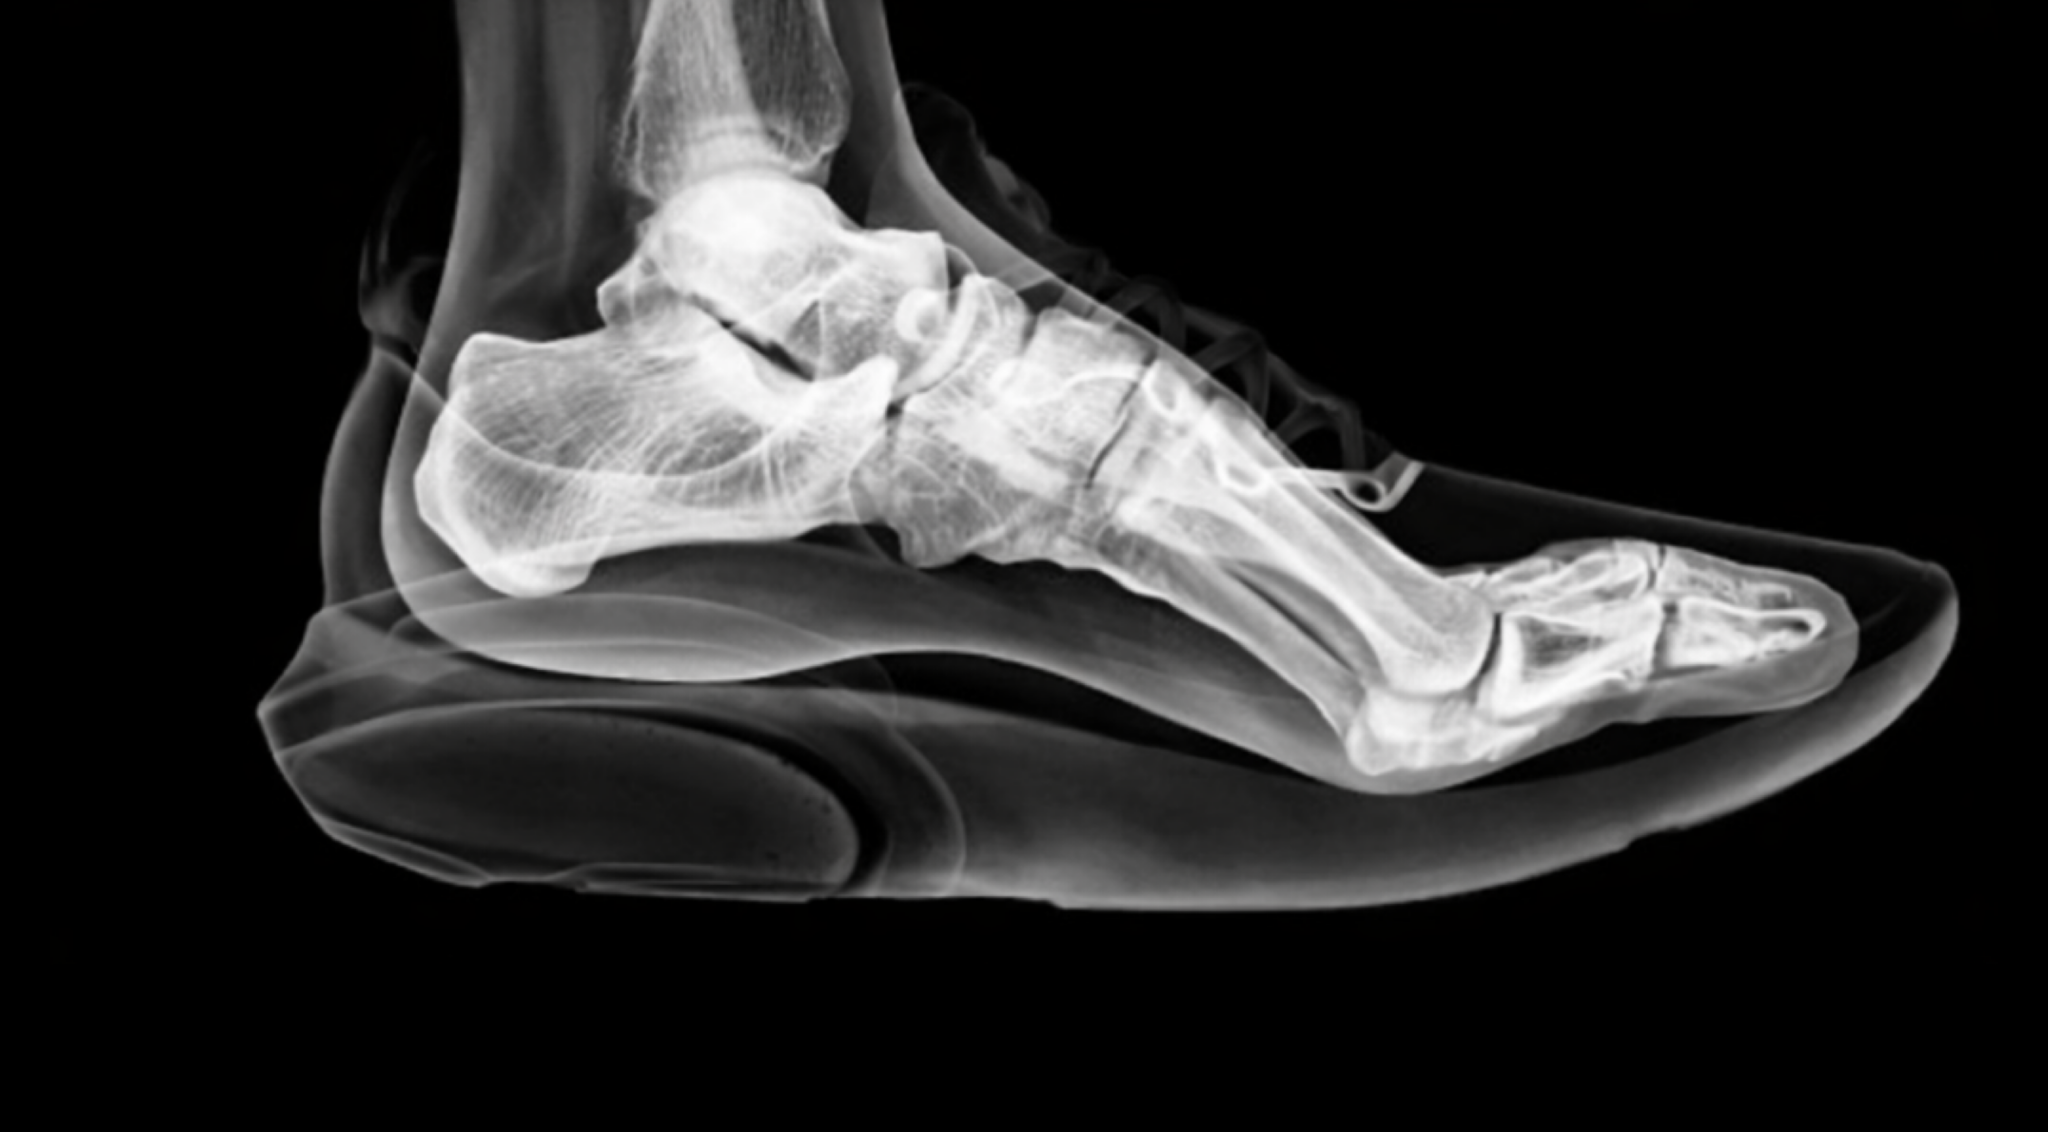

なぜなら外反母趾は、

靴の中で 足がどう使われているか によって進行するからです。

外反母趾は「靴で曲がる」のではなく「靴の中の使われ方」で決まる

外反母趾は、

靴が当たるから

圧迫されるから

という 外的刺激だけ で起きているわけではありません。

多くの場合、

・靴の中で足が滑る

・足指が地面を押せない

・前足部の足底圧が抜ける

・重心が内側に逃げる

という 力学的な崩れ が先に起きています。